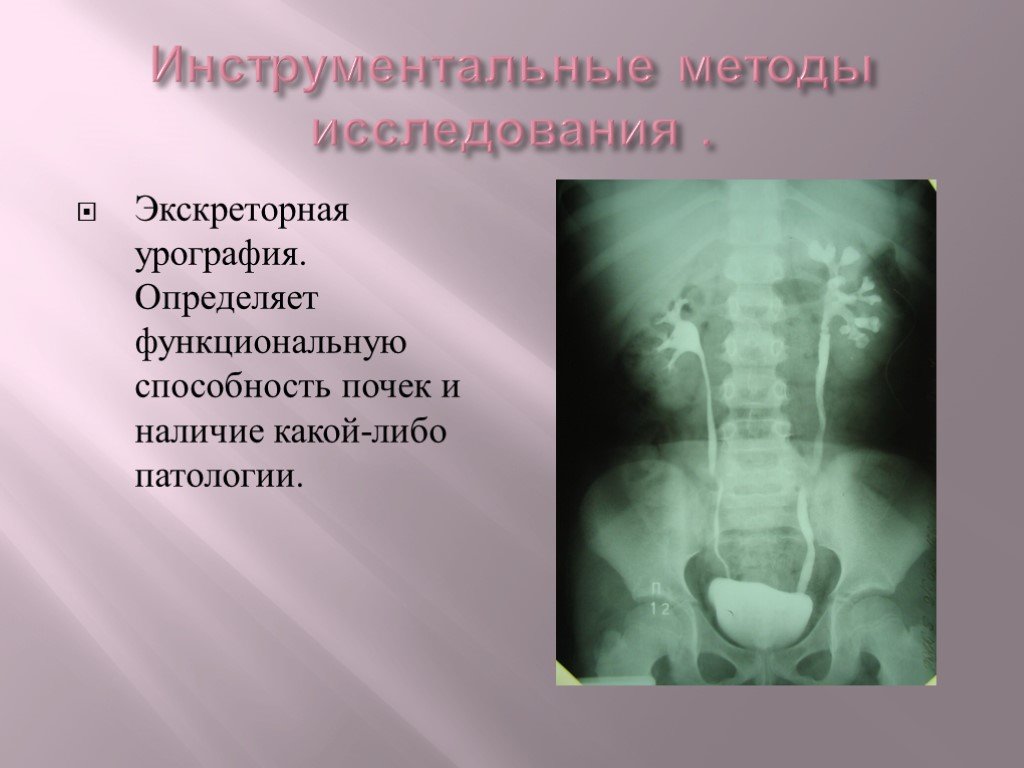

Медицинские изображения и примеры эксреторной цистографии